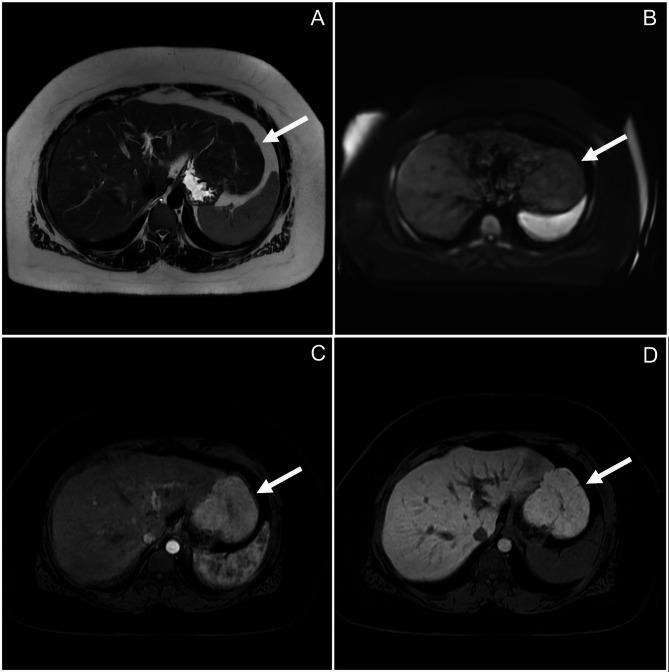

We describe a 33-year-old female who underwent excision of a pedunculated FNH. On gross examination, the lesion was lobular and vascular with homogenous tan-brown surfaces. Histological examination showed loss of normal liver architecture, abnormal intervening fibrous tracts, dysplastic arteries, and focal steatosis. Immunohistochemical staining with glutamine synthetase resulted in a branching, or "map-like" pattern. These findings were consistent with focal nodular hyperplasia. One of the most sensitive imaging techniques for diagnosing this lesion involves magnetic resonance imaging (MRI) with contrast, which discloses a homogenous mass that is hyperintense during the arterial phase with gradual decrease in intensity during the venous and equilibrium phases. The central stellate scar will often remain hyperintense for a prolonged period of time. On histology, normal hepatic architecture is lost to abnormal fibrotic bands and a characteristic stellate scar. Immunohistochemistry with glutamine synthetase uniquely highlights a map-like pattern that is not seen in other liver lesions.

我们描述了一名33岁接受带蒂FNH切除手术的女性。大体检查时,病变呈小叶状且血管丰富,表面为均匀的棕褐色。组织学检查显示正常肝结构消失,有异常的间质纤维束、发育异常的动脉和局灶性脂肪变性。谷氨酰胺合成酶免疫组化染色呈现分支状或“地图样”图案。这些发现符合局灶性结节性增生。诊断该病变最敏感的影像学技术之一是增强磁共振成像(MRI),其显示一个均匀的肿块,在动脉期呈高信号,在静脉期和平衡期信号强度逐渐降低。中央星状瘢痕通常会在较长时间内保持高信号。在组织学上,正常肝结构被异常纤维化带和特征性星状瘢痕取代。谷氨酰胺合成酶免疫组化独特地突出了一种在其他肝脏病变中未见的地图样图案。